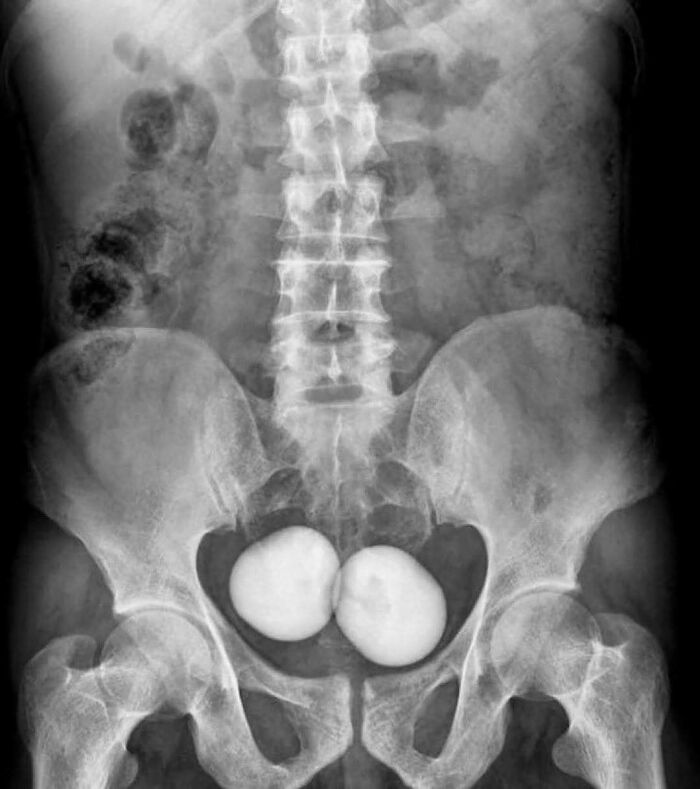

#27

KUB X-ray shows two large and oval radio-opaque shadows in the pelvis